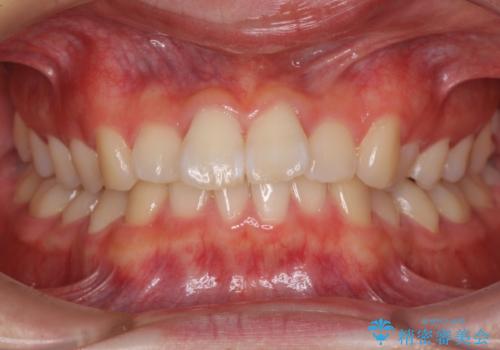

海外留学をしながら歯並びを整えたい インビザラインによる矯正治療

【モニター】 インビザラインによる後戻りの再矯正治療